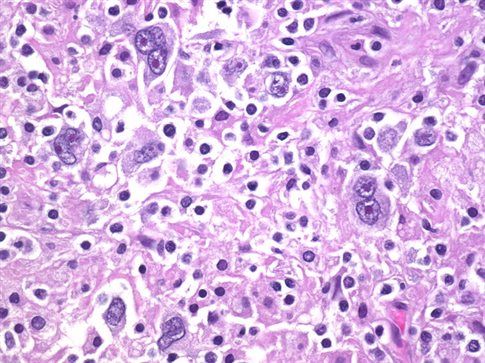

Το λέμφωμα Hodgkin είναι ένας από τους πιο συχνούς καρκίνους στα παιδιά και στους νέους ενηλίκους. Αν και συχνά η νόσος αντιμετωπίζεται αποτελεσματικά με τις υπάρχουσες θεραπείες, περίπου το ένα τέταρτο των ασθενών τελικά υποτροπιάζουν.

Ωστόσο, τα δύο νέα σκευάσματα ενισχύουν το ανοσοποιητικό σύστημα του ασθενή, ώστε να καταστρέψει τα καρκινικά κύτταρα του λεμφικού ιστού.